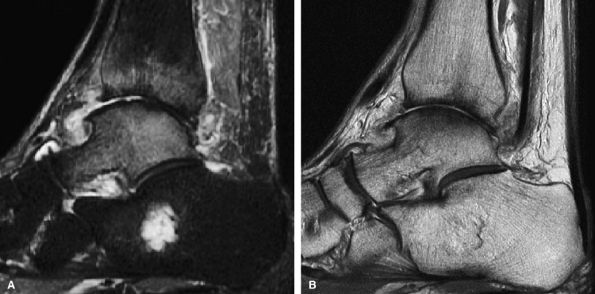

FIGURE 7.19 ● (A) Sagittal fat-suppressed MR image of the ankle in a 64-year-old man with OA of the tibiotalar joint demonstrates bone marrow edema pattern over both sides of the joint. (B) The corresponding cartilage-sensitive MR image demonstrates full-thickness cartilage loss, anterior osteophyte formation, and subchondral sclerosis. The presence of bone marrow edema over both sides of a joint in the setting of OA does not indicate superimposed fracture or osteonecrosis.

FIGURE 7.21 ● Sagittal (A) and coronal (B) fast spin-echo MR images of the ankle in a 16-year-old patient demonstrate an osteochondral shearing injury (arrows) over the anterior margin of the tibial plafond. A free cartilaginous fragment (arrowhead) in the anterior recess is present. Cartilage over the talar dome is preserved.